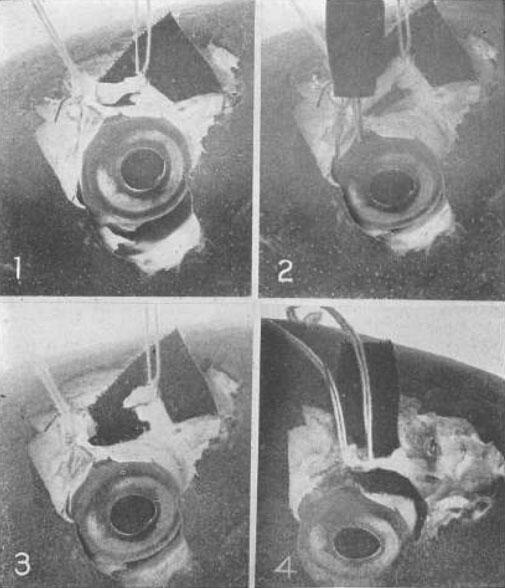

Рис. 13. Демонстрация на примере глаза кролика того, что нижняя косая мышца является существенным фактором в процессе аккомодации

1 Нижняя косая мышца была подвержена воздействию электрическим током, и две нити были присоединены к ней. Стимуляция глазного яблока электрическим током вызвала аккомодацию, как показала симультативная ретиноскопия.

2 Мышца была разрезана. Стимуляция электрическом током не вызывает аккомодации.

3 Концы разрезанной мышцы сшиты друг с другом. Стимуляция электрическим током способствует возникновению нормальной аккомодации